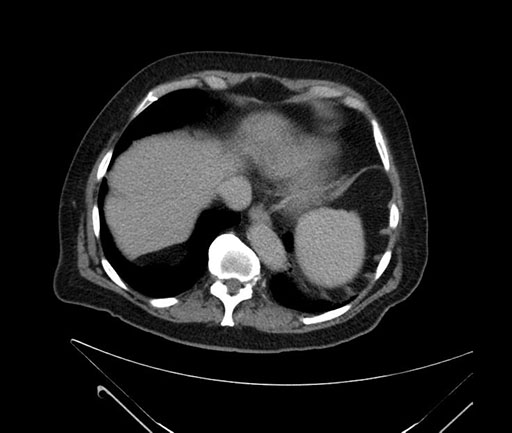

Whipple (pancreaticoduodenectomy) [case 7]

Imaging Analysis

Look through the patient's CT scan to identify any areas of concern for the necessary procedure.

Based on your CT findings, which issue(s) would give reason for "planned slowing down moment(s)" in this case?

Considering a standard Whipple procedure, what step(s) of the operation would you do differently in this case?